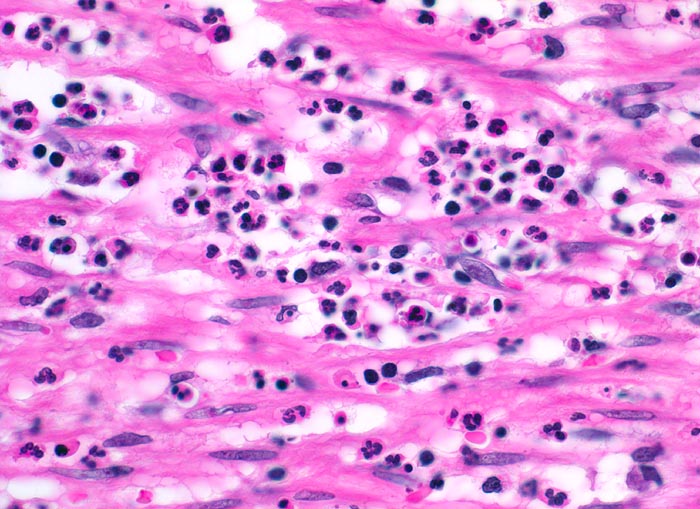

akute Appendizitis: phlegmonöse Entzündung

Entzündung / Reparatur

Appendix vermiformis

Die glatte Muskulatur der Appendixwand wird diffus infiltriert von neutrophilen Granulozyten.

Seit 6 Stunden Schmerzen im Unterbauch rechts mit zunehmender lokaler Druckempfindlichkeit. Übelkeit.

Histologie

400